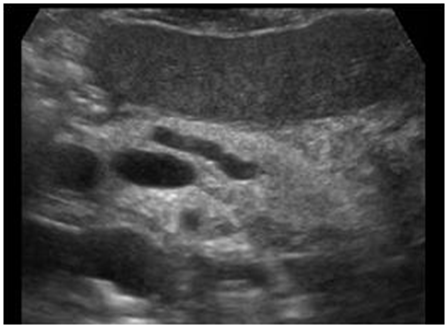

The pancreatic echo sonography must be well done, fully showing the morphology of the páncreas, the best plane in the transversal in the upper abdomen, in deep inspiration, observing the head, body and tail in front of the splenic vein (Figure 1). It is very important to note superior mesenteric artery, because this vessel divides the páncreas in a cefalo-corporal and a corpocaudal areas, 75% of neoplasms of the páncreas are in the first zone and 25% in the second. In preparation for this test, antiflatulents the previous day should be used to avoid artifacts gas in the stomach, duodenum and splenic flexure of the colon, causing inadequate observation. We use the RULE OF THREE: All pancreatic size greater than 3 centimeters is abnormal and should be studied. All pancreatic duct greater than 3 millimeters is abnormal and should be studied.

Figure 1 Head, body and tail of the normal pancreas.